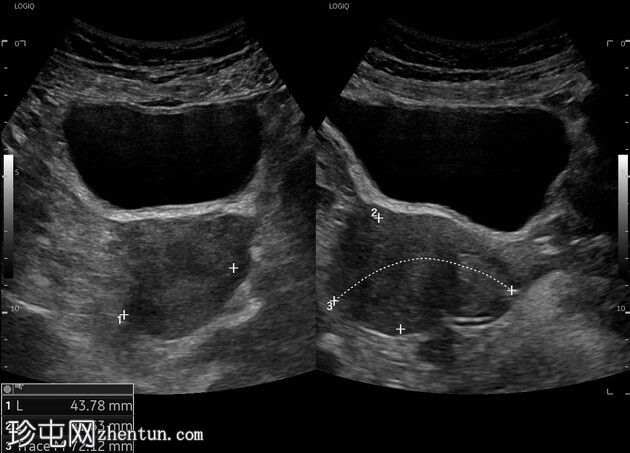

超声

3.jpeg

多切面

经腹超声显示膀胱充盈(排尿前尿量160毫升),膀胱壁无增厚。未见管腔内结石。未见膀胱输尿管连接处结石或水肿。左肾结石(7毫米),无肾积水。右肾下盏饱满,无盆腔饱满。双侧输尿管均未见扩张。排尿后尿量为125毫升。